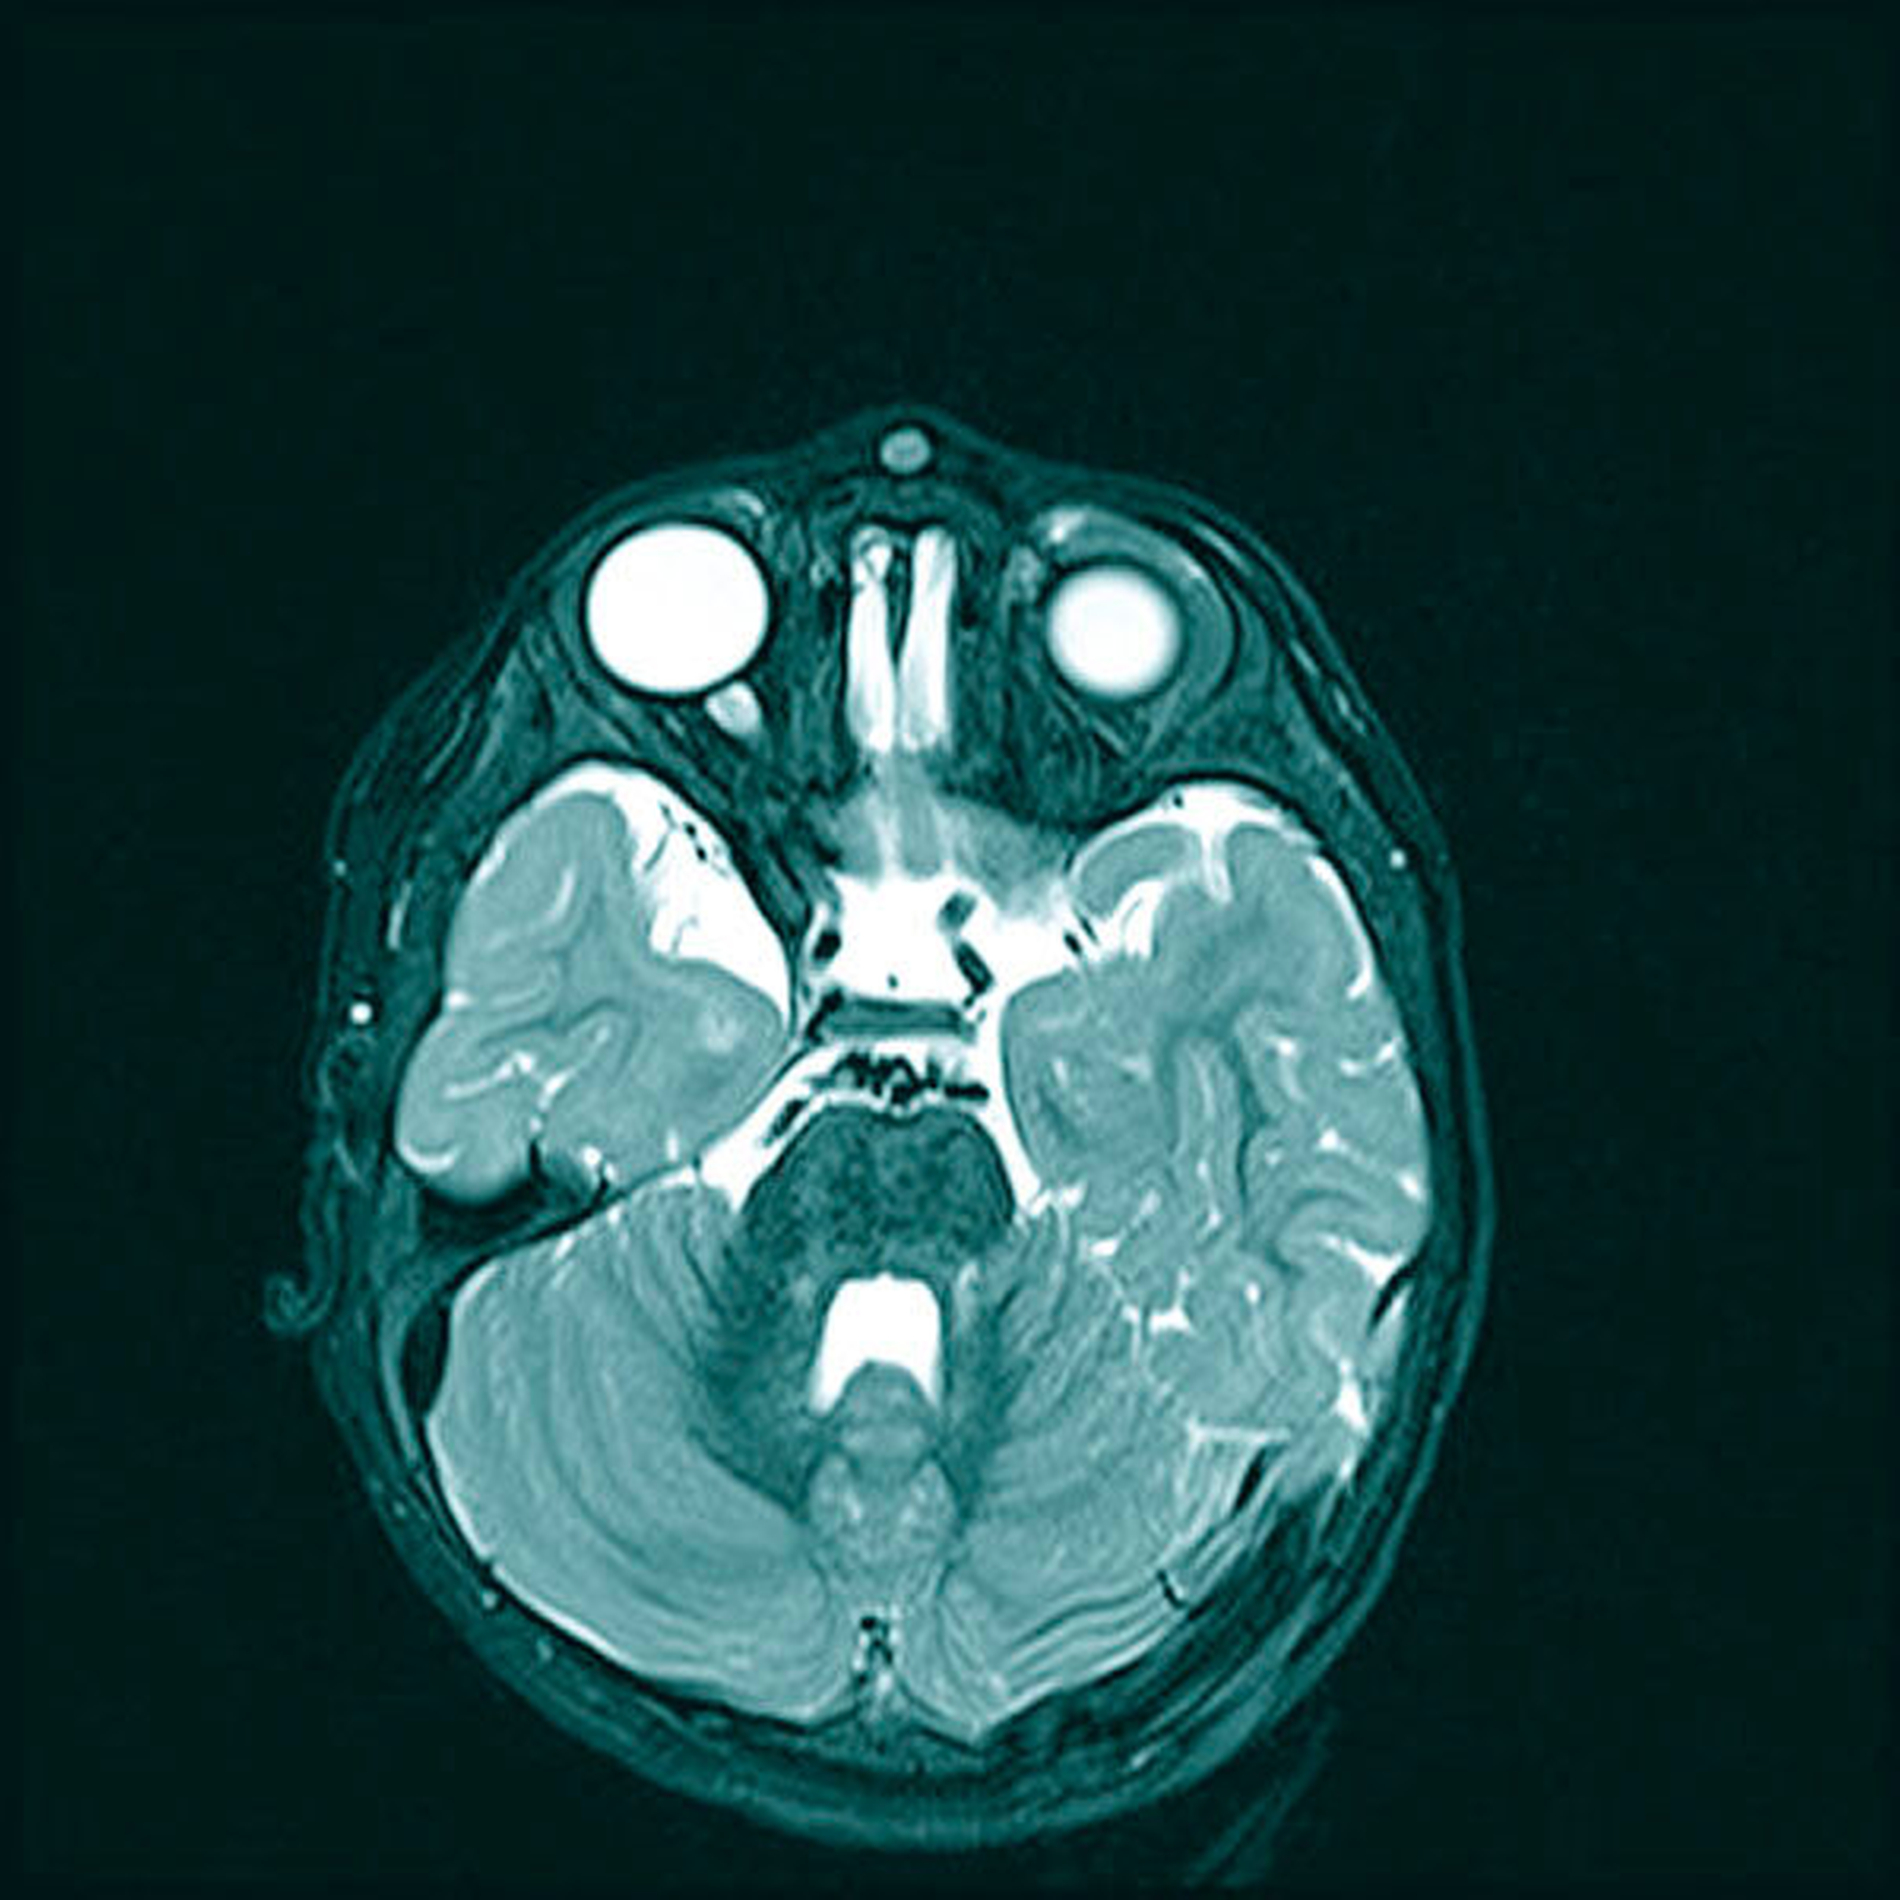

Im MRT bestätigte sich das Vorliegen einer umschrieben-bekapselten, rundlichen Formation median an der Glabella. Der Tumor war inhomogen hypointens in der T1- und hyperintens in der T2-Wichtung (Abbildungen 2 und 3). Des Weiteren stellte sich eine leicht imprimierte Tabula externa der angrenzenden Kalotte ohne Nachweis einer intrakraniellen Ausdehnung dar (Abbildung 4). Somit erhärtete sich der Verdacht auf Vorliegen einer Epidermoid- beziehungsweise einer Dermoidzyste und nach Rücksprache mit den Eltern erfolgte die chirurgische Entfernung.